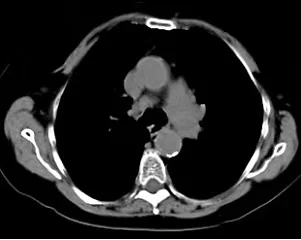

CT Scans

A computerized tomography scanner creates cross-sectional images of the body which provide more detailed information than standard X-ray images. CT images delineate the soft tissues, blood vessels, and bones in various parts of the body. Among its many uses, CT scans may be utilized to diagnose infections or bone fractures. It may also be used to pinpoint the location of masses and tumors (including cancer), study the blood vessels and other internal structures, assess the extent of internal injuries and internal bleeding, guide procedures, such as surgeries and biopsies and monitor the effectiveness of treatments for certain medical conditions, including cancer and heart disease. CT scans are performed with and/or without contrast.